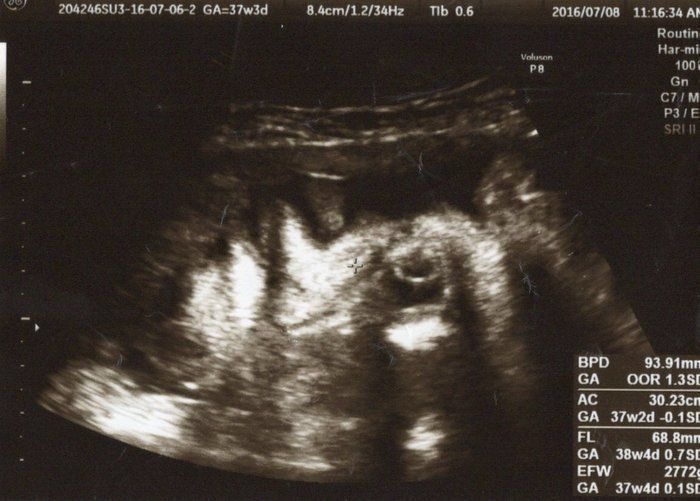

Tomomiさんの妊娠37週目のエコー写真 妊娠高血圧症候群で緊急帝王切開!

予定していた手術日を延期にして、もう少し体調を整えようとしていた矢先、今度は妊娠高血圧症候群になりました。その日の朝まで慌ただしく家事・育児をしていたのに、突然のめまいや吐き気に襲われ診察に行くと、「母体が危険な状態」と言われ、そのまま地域の医療センターへ転院となりました。手術直前のエコーでは、久しぶりにお顔を見せてくれましたが、私はそれどころではなく…。でもよく見ると、息子も少し苦しそうなお顔をしているような気がしますね。